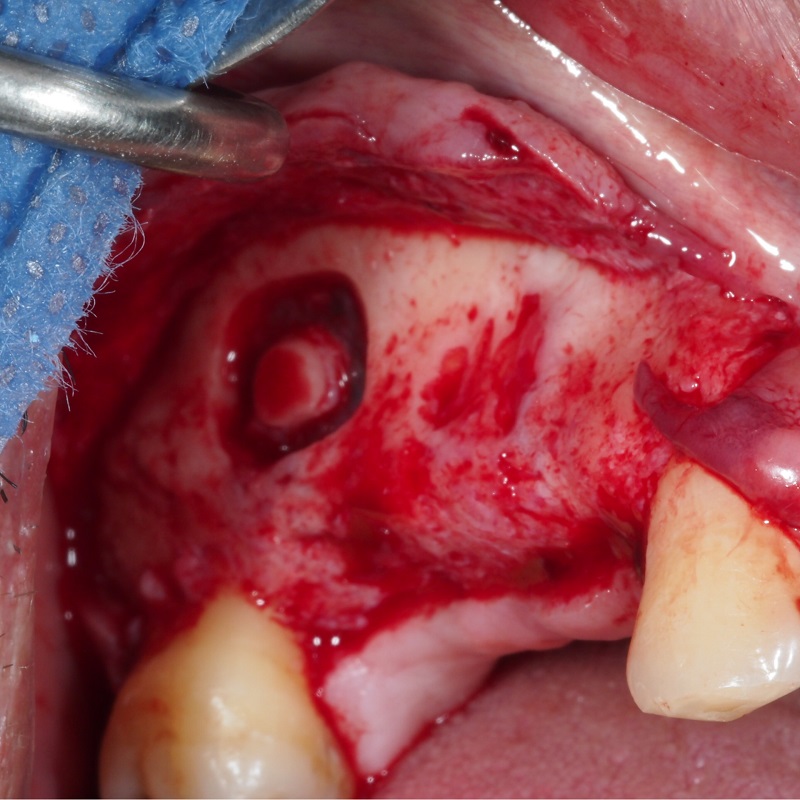

- Apertura de ventana lateral en seno maxilar

- Elevación de la membrana de Schneider